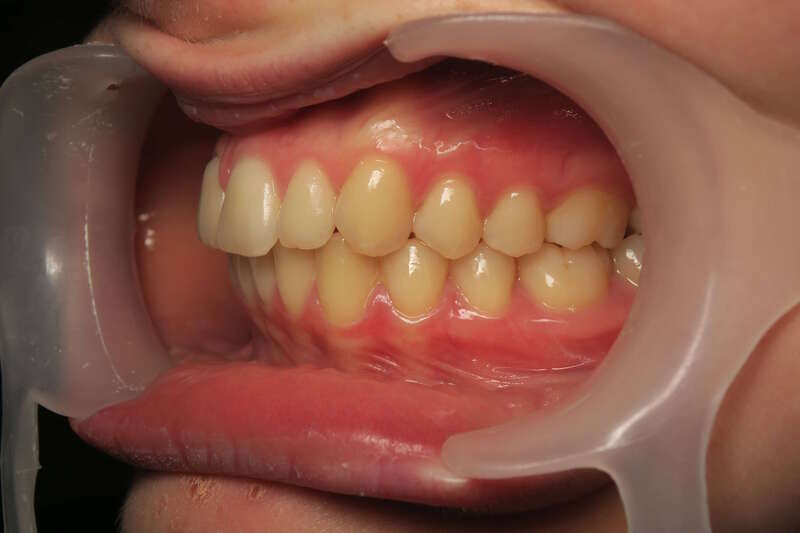

Cas n°9 traité par multi-attaches - adolescent

Ce cas d'adolescent illustre une stratégie de développement d'arcade réussie. Le patient présentait un encombrement massif et des inversions d'articulé rendant l'occlusion instable.

Le traitement a été réalisé avec des multibagues autoligaturantes, choisies pour leur capacité à générer des forces légères et continues, idéales pour l'expansion transversale. Cette approche a permis de corriger l'encombrement et les inversions d'articulé sans extractions dentaires, en remodelant simplement la forme des arcades.

Résultats clés :

• Transformation d'arcade : Passage d'une arcade étroite et encombrée à une arcade large et fonctionnelle.

• Occlusion optimale : Rétablissement d'un engrènement sain, protégeant les dents contre les usures anormales.

• Esthétique naturelle : Le sourire est élargi, harmonieux et parfaitement intégré au profil du patient.

C'est une démonstration de l'efficacité biologique de l'orthodontie moderne, qui privilégie la conservation dentaire et le respect des structures osseuses.